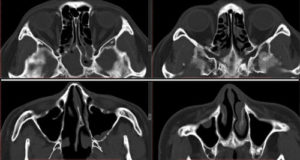

Единственными методами, которые наверняка могут определить сфеноидит, являются компьютерная томография (КТ) или магнитно-резонансная томография (МРТ) –